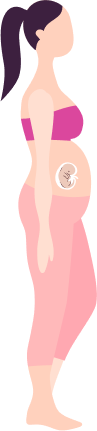

Why you haven’t conceived yet: menstrual history, male factor, egg reserve, age, previous treatments.

Is it timed intercourse, ovulation induction, IUI, Green IVF, conventional IVF, laparoscopy, or just lifestyle correction? We tell you the shortest, safest path — not the costliest one.

You’ll know exactly what to do in the next 30–60 days - scans, blood tests, diet, partner tests.

For women who don’t want heavy injections or very high-cost IVF, Srushti pioneered a gentler path that still gives excellent outcomes for selected patients.

Polyps, fibroids, endometriosis, tubal blocks – many of these can be corrected with hysteroscopy/laparoscopy so that you can try naturally/IUI first instead of jumping to IVF.

Fertility is not only “female.” We run male fertility assessments too and create a plan for the couple, not just one partner. This is why our cycles show higher success.